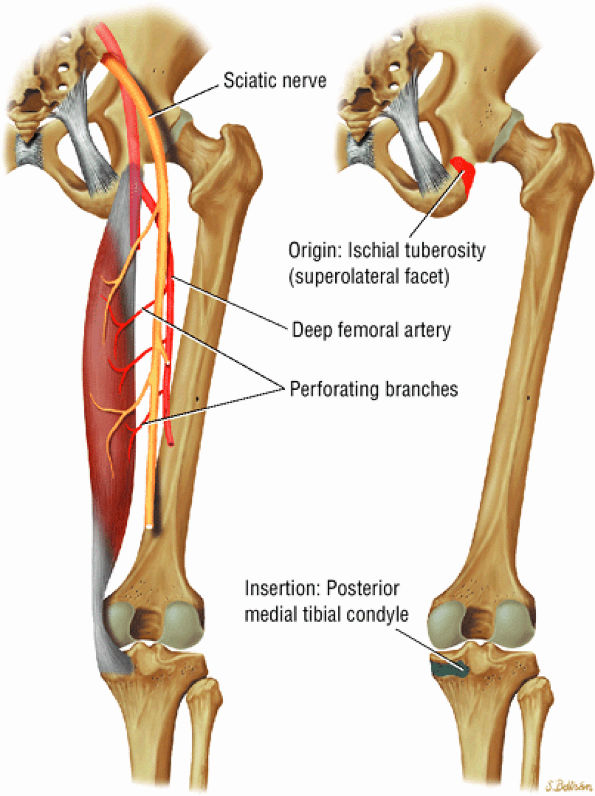

The posterior muscles of the thigh, including the biceps femoris (Fig. 3.25), the semimembranosus (Fig. 3.26), and the semitendinosus (Fig. 3.27).

FIGURE 3.25 ● BICEPS FEMORIS The biceps femoris extends the thigh and flexes the leg in external rotation of the tibia, contributing to lateral stability of the knee. The muscles of the hamstring group (biceps femoris, semimembranosus, and semitendinosus), except for the short head of the biceps femoris, all cross the hip and the knee joint. Musculotendinous junctions extend the entire length of the muscle and serve as potential sites for strains. The short head is innervated by the peroneal branch of the sciatic nerve; the other hamstring muscles derive innervation from the tibial branch of the sciatic nerve.

FIGURE 3.26 ● SEMIMEMBRANOSUS The semimembranosus extends the thigh and flexes the leg. It is part of the hamstring muscle group (biceps femoris, semimembranosus, and semitendinosus) in the posterior thigh. Except for the short head of the biceps, the origins of the hamstring tendons are from the ischial tuberosity and are involved in ischial avulsion fractures in the young athlete.

FIGURE 3.27 ● SEMITENDINOSUS The semitendinosus, which is part of the hamstring muscle group, extends the thigh and flexes the leg. It may be used for anterior cruciate ligament reconstructions, posterolateral knee reconstructions, and tenodesis for patellar subluxation. It is the most posteromedial tendon on axial knee images at the joint line. Hip hyperflexion and simultaneous knee extension is a mechanism of injury for proximal hamstring injuries in adults and apophyseal avulsions in young skeletally immature athletes.